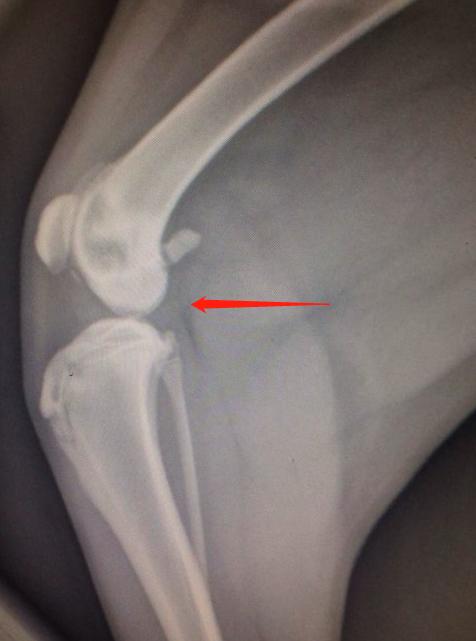

关节软骨无法在特定位置转变为骨骼,直接令到这区域的软骨增厚,增厚的软骨与周围正常的软骨分离形成了皮瓣,这一系列过程便称之为OCD。异常软骨的皮瓣有可能会发生从关节表面脱离,形成“关节鼠”。

图为“关节鼠”

那么,什么是“关节鼠”?

这一术语较好理解,意指关节出现病变的时候,在关节软骨内部会有自行脱离的“小碎片”。如前文提到,关节之间有“小碎片”的存在,容易发生疼痛等一系列影响。

膝关节骨软骨病